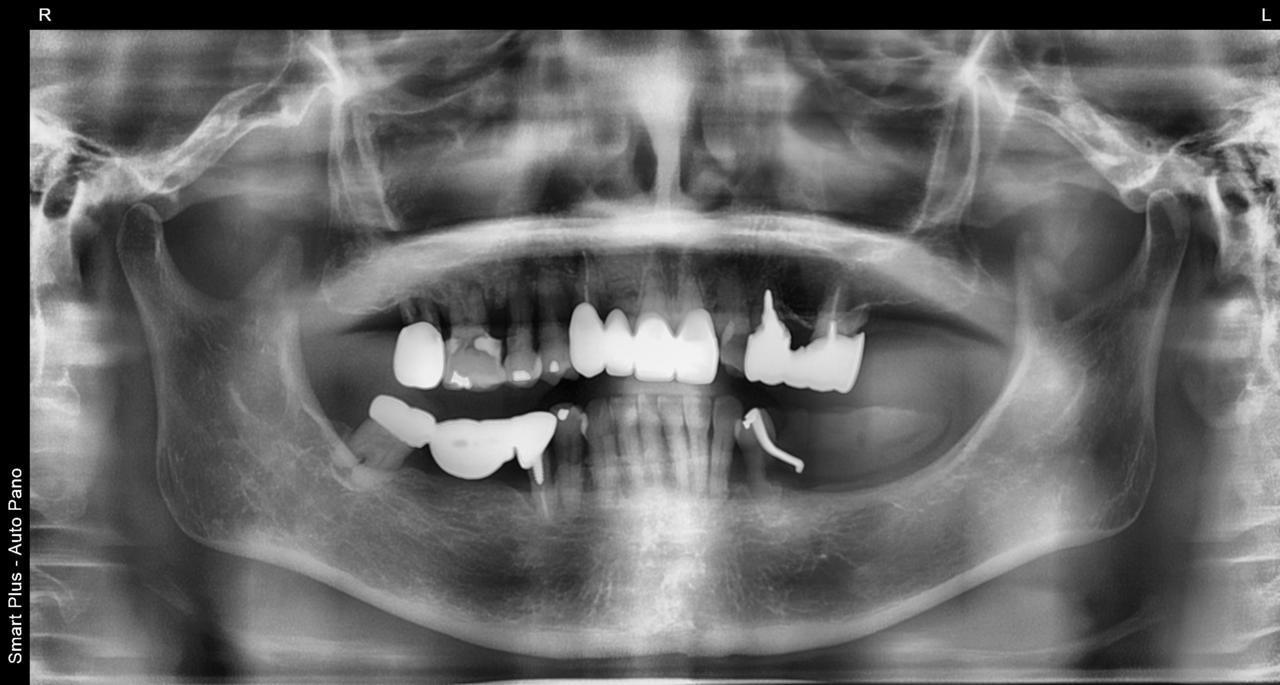

Before

枚方市のインプラントの症例

K・S様 女性 60代

症状としては、 右上4から7番までのすべての歯の著しい動揺があり、食事が困難であった。

治療法としては、患者様は、患者様が3か月以内の治療完了を望んでいたために、炎症が若干あったが、右上4から7番ぼすべての抜歯を行い、右上4番(抜歯即時埋入)、右上6番(上顎洞までの骨がほとんどないため、グラフトレスサイナスリフト施行)にインプラントを1回法で手術を終え、2か月半後にインプラントの状態が安定したために、3か月で上部構造の、右上456のジルコニアブリッジを装着して、治療を終えています。

治療結果としては、抜歯したと同時にインプラントを埋入することで、抜歯した穴が自然に治る過程で、インプラントの骨結合と組織の治癒が同時に行われるために、3か月という治療期間で治療を終了することができたことと、機能面・審美面でも回復を行うができた。また、右上6番に関しては、グラフトレスサイナスリフトを行うことで、従来のサイナスリフトに比べ、約9か月早く治療を終えることができました。

治療の期間・回数:約3か月、インプラント抜歯即時埋入から最終補綴物装着まで8回

治療の価格:792000円(税込)

治療費の内訳:インプラント基本料(フィックスチャー(メガジェンインプラントANYONE使用) 及び手術費用、投薬費用、レントゲン費用、インプラント上部費用(アバットメントおよびジルコニアクラウンの費用用)330000円×2 660000円(税込み)。オプション、抜歯即時埋入加算(人工骨費用を含まず)5500円×2 11000円(税込み)右上5ジル9コニアブリッジのポンテック費用 88000円 右上6グラフトレスサイナスリフト費用 33000円(税込み

治療のリスクや副作用:手術後に、痛みや腫れ、出血、合併症などを引き起こす可能性があります。噛む感覚がご自身の歯と異なる場合があります。見た目がご自身の歯と異なる場合があります。手術後にメインテナンスを継続しないと、インプラントが抜け落ちる可能性があります。